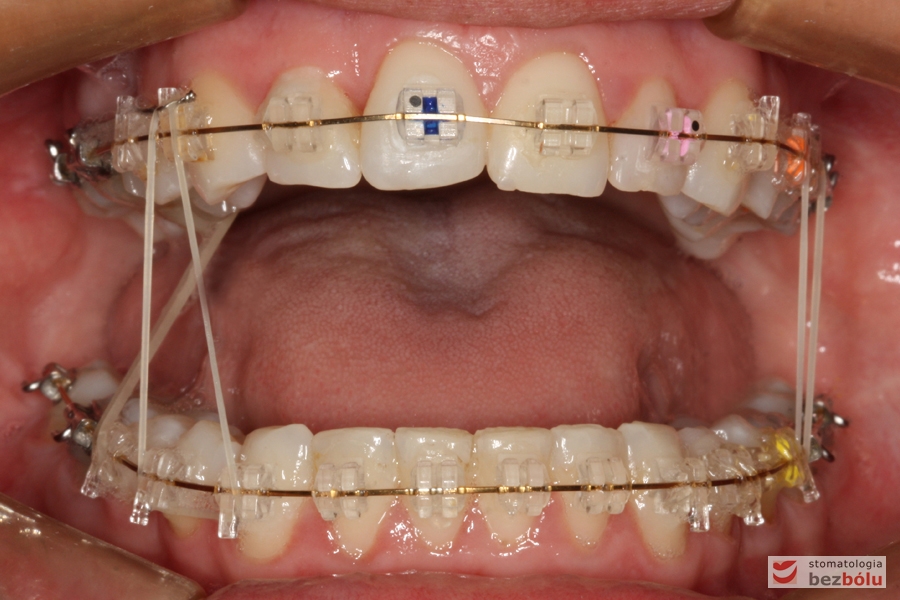

Cienkołukowy aparat estetyczny

Cienkołukowy aparat estetyczny - zastosowanie elastycznych wyciągów wewnątrzustnych

Cienkołukowy aparat estetyczny – zastosowanie elastycznych wyciągów wewnątrzustnych